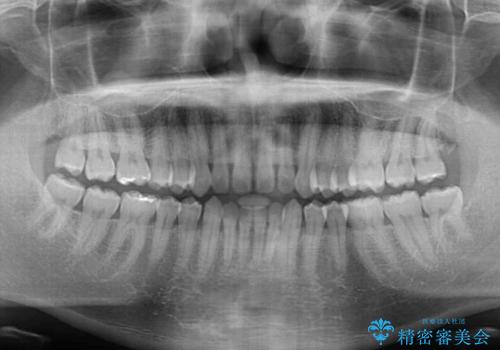

- 上の前歯の隙間を気にして来院された患者様です。

インビザラインにより、上下の歯列を側方に拡大しつつ、前歯の隙間を閉じていくこととしました。

1日22時間の装着時間をしっかりと守ってくださったので、隙間がきれいに閉じ、口元の突出感も改善することができました。